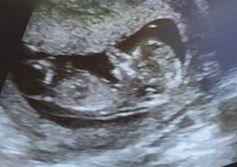

This is the nub of Bub #2

We are thinking its a girl this time because the nub (the first white line is the cord) is very parallel with the spine. Doesn't look risen.

My son and this baby look completely different, my son had a clear risen willy at 12 weeks.

When I saw a potty shot it was round and I saw a couple lines. My son had testicles on his one